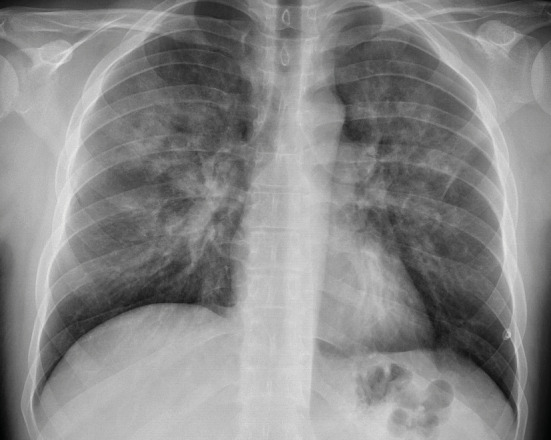

七氟醚是一种常用的吸入麻醉剂,用于诱导和维持全身麻醉。然而,它与一种罕见但严重的肺部疾病--弥漫性肺泡出血(DAH)--有关。弥漫性肺泡出血的特点是血红蛋白水平下降、弥漫性肺浸润以及伴有低氧血症的呼吸衰竭。我们介绍了一例在一次并不复杂的骨科手术中使用吸入七氟醚进行全身麻醉后出现 DAH 的健康年轻成人。值得注意的是,该患者没有其他风险因素或已知病因可能导致 DAH 的发生。

Sevoflurane is a commonly used inhalational anesthetic agent for inducing and maintaining general anesthesia. However, it has been associated with a rare but serious pulmonary condition known as diffuse alveolar hemorrhage (DAH). DAH is characterized by decreased hemoglobin levels, diffuse pulmonary infiltration, and respiratory failure with hypoxemia. We present a case of DAH in a healthy young adult who experienced this condition following general anesthesia with inhaled sevoflurane during an uncomplicated orthopedic procedure. Notably, there were no other risk factors or known causes that could account for the development of DAH in this patient.